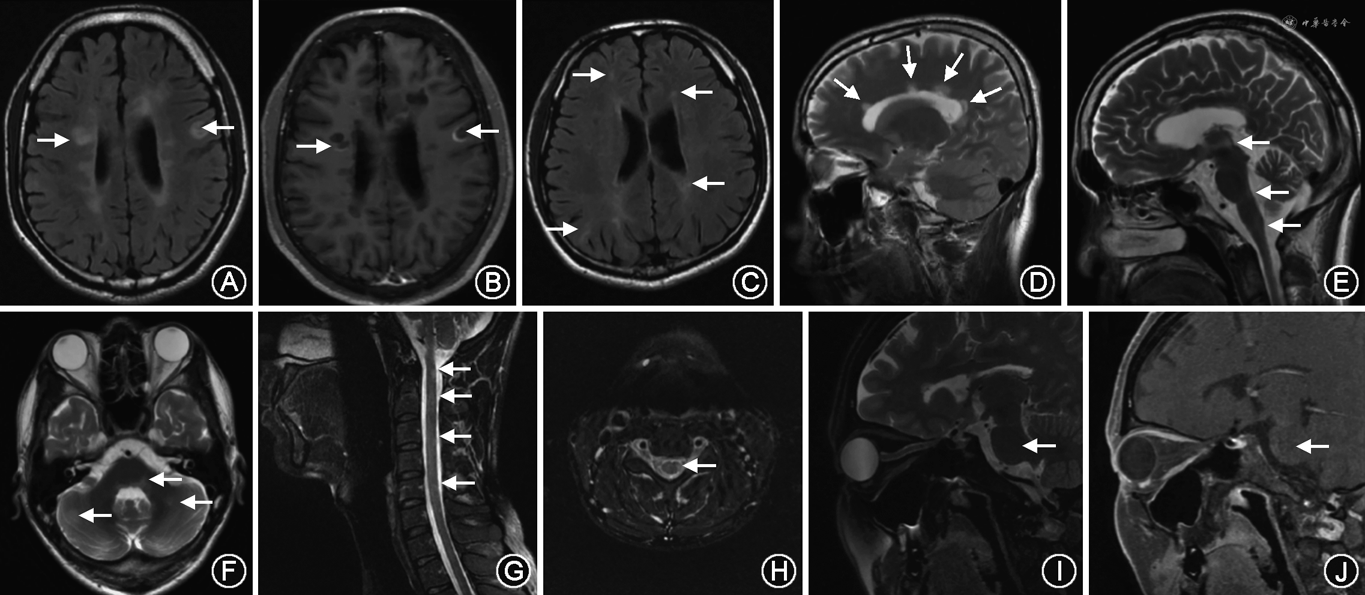

2017年新版的McDonald MS诊断标准和2015年MAGNIMS MS MRI诊断标准有很多共同点,如与既往指南相比,都纳入了皮质病灶、幕下/脊髓症状性病灶等。两版指南也均有相似的推荐,如2017年McDonald MS诊断标准建议年龄较大和有脑血管病基础的患者需要增加脑室旁病灶的数量[2],而2015年MAGNIMS MS MRI诊断标准建议增加脑室旁病灶数量至≥3个[3]。二者的不同点主要在于2015年MAGNIMS MS MRI诊断标准纳入了视神经MRI病灶,使MS的CNS典型受累区域增加至5个[3](图1),而2017年McDonald MS诊断标准认为视神经MRI病灶对MS具有诊断意义的证据尚不充分[2]。此外,2017年McDonald MS诊断标准[2]对于PPMS有其独立的诊断标准,而2015年MAGNIMS MS MRI诊断标准建议对PPMS和复发型MS采用相同的DIS标准,并建议对于临床不确定的PPMS患者应考虑将脑脊液结果作为诊断参考[3]。

| 头颅MRI | 脑室旁(毗邻侧脑室的大脑白质病变,直角征)、皮质/近皮质(大脑皮质内的病灶/大脑白质病变,毗邻皮质)、幕下(脑干病灶通常靠近表面、小脑脚或小脑),圆形、类圆形病变 | 延髓最后区、第三和第四脑室周围、下丘脑、丘脑病变,皮质下或深部较大融合的白质病变,胼胝体病变较长较弥散(>1/2 胼胝体)、沿锥体束走行对称较长病变 | 多发或单发白质病灶,斑片状,可伴有丘脑、海马、皮质/近皮质病灶,大病灶肿瘤样,可见软脑膜受累 |

| 脊髓MRI | 短节段病灶;偏侧 | 长节段病灶(纵向延伸超过3个椎体节段);中央 | 长或短节段病灶,横断面可见于中央或周边,累及腰髓/圆锥为相对特异性表现 |

| 视神经MRI | 短节段病灶 | 长病灶(长于视神经的1/2),视神经后段或视交叉病灶 | 长病灶(长于视神经的1/2),视神经前段病灶 |